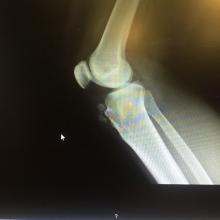

More Knee Replacements at Younger Ages

The National Hospital Discharge Survey shows that between 2000 and 2010, more than 5.2 million total knee replacements were performed in the United States. By 2010, the operation had become the leading inpatient surgery performed on adults aged 45 and over. Moreover, the rate at which middle-aged and older Americans got their knees replaced almost doubled over the study period.